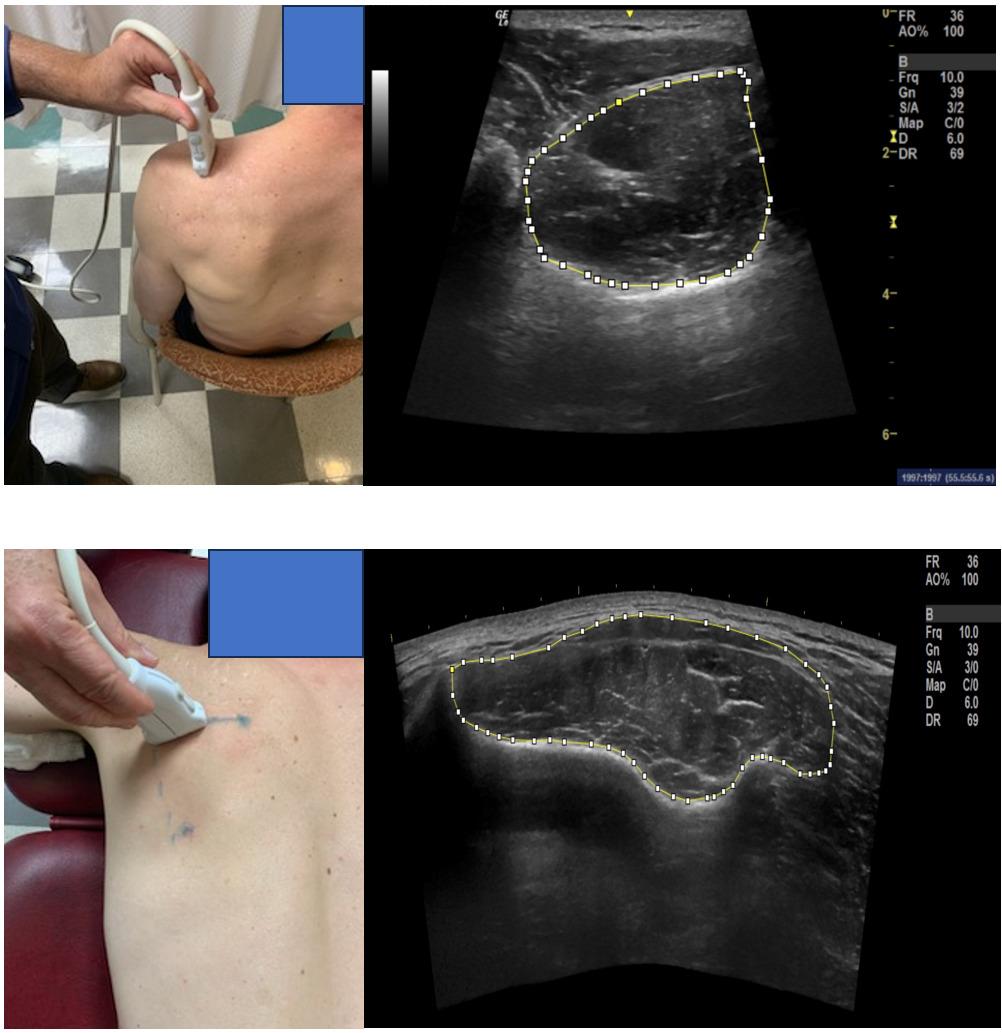

768 Use of Diagnostic Musculoskeletal Ultrasound in the Evaluation of Piriformis Syndrome: A Review for Rehabilitation Providers.

Manske RC, Wolfe C, Page P, Voight M, Bardowski B.